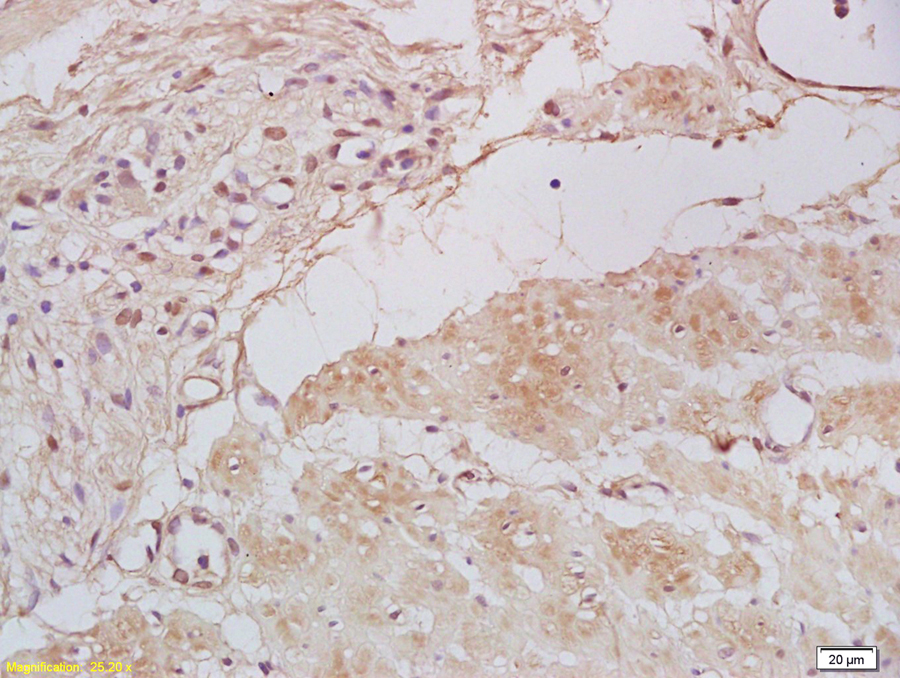

Tissue/cell: human gastric carcinoma; 4% Paraformaldehyde-fixed and paraffin-embedded; Antigen retrieval: citrate buffer ( 0.01M, pH 6.0 ), Boiling bathing for 15min; Block endogenous peroxidase by 3% Hydrogen peroxide for 30min; Blocking buffer (normal goat serum,C-0005) at 37℃ for 20 min; Incubation: Anti-Tbx21/T-bet Polyclonal Antibody, Unconjugated(bs-3599R) 1:200, overnight at 4°C, followed by conjugation to the secondary antibody(SP-0023) and DAB(C-0010) staining